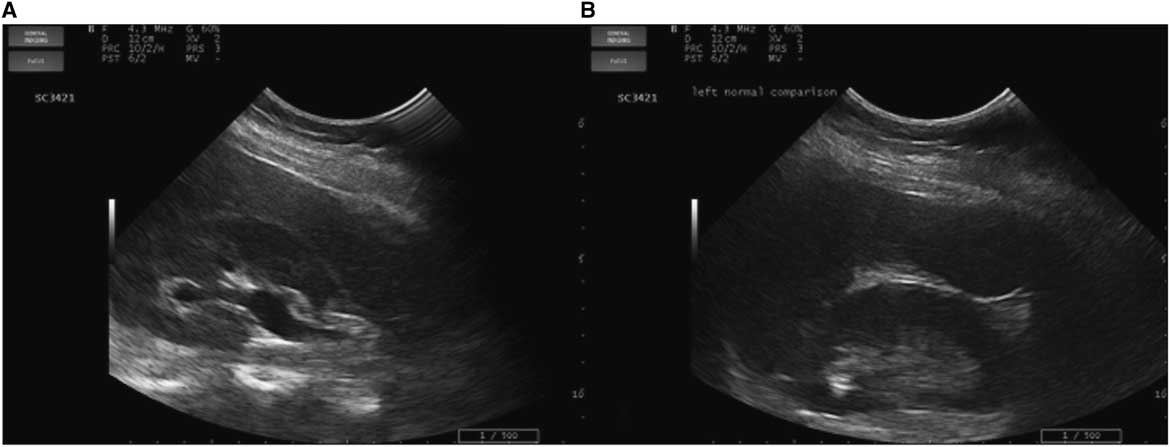

As the clinical course (demonstrated by intractable flank pain) failed to improve over 5 hours with symptomatic therapy and the diagnosis of renal colic yet to be confirmed, an abdominal and pelvic CT was ordered. This study revealed a small 5-mm distal obstructing ureteric calculus at the right vesicoureteric junction causing proximal moderate hydroureteronephrosis (Figure 2). Coincidentally, the CT also revealed another 5-mm left proximal ureteric calculus at approximately the level of the L3 vertebra causing mild ipsilateral proximal hydroureter.

Figure 2 CT axial views. A) Enlarged right kidney indicative of hydronephrosis (circle) compared to the left. B) A 5-mm right distal ureteric calculus at the right vesicoureteric junction (arrow). C) A 5-mm left proximal ureteric calculus (arrow).